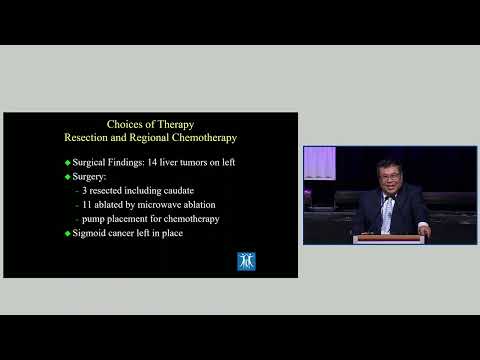

KN01: Palliative Liver Resection

Keynote Lecture 01: Palliative Liver Resection